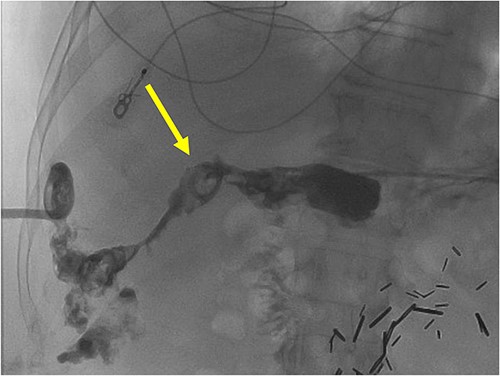

The patient is a 72-year-old male who underwent laparoscopic cholecystectomy for gangrenous cholecystitis at an outside hospital 23 months prior to our initial visit. Other pertinent medical history included ischemic stroke with resultant speech/vision deficits and left-sided hemiparesis, bladder cancer, testicular cancer, and colon cancer. His surgery was complicated by recurrent liver abscesses diagnosed 7 months postoperatively. He was treated with antibiotics and underwent multiple image-guided percutaneous drainages in the 9 months after his index operation. Unfortunately, many failed intravenous and oral courses of broad-spectrum antibiotics had resulted in treatment resistant Clostridium difficile infection, requiring stool transplant for successful eradication of his colonic infection. He presented to the emergency department 1 day after a drain placement procedure with complaints of right upper quadrant abdominal pain, nausea, and emesis. Similar to the first case presented in this report, the oral contrast administered during prior abdominal CT scan was unable to demonstrate this fistulous connection. Fistulogram performed through the abdominal drains demonstrated a fistulous connection between the abscesses and the gastric antrum (Fig. 4). Additionally, two small cutaneous fistulae in the right abdominal wall were identified, draining the overflow purulence from the perihepatic abscess cavities through the skin. He underwent endoscopic closure of the gastro-perihepatic fistula using the over-the-scope clip, followed by intraoperative abdominal wall fistulae washout 5 days later (Fig. 5). Both fistula cavities were packed with cotton packing strips, and the percutaneously placed drains were removed. He was discharged with oral antibiotics. Repeat CT scans at 1 and 3 months postoperatively demonstrated smaller perihepatic abscesses. Patient reported no symptoms of recurrence of abscesses or fistulae. The abdominal wall fistulae had decreased purulent drainage and continued to be managed with wet-to-dry packing.

A radiographic fistulogram demonstrating the fistulous tract communicating with the proximal duodenum/gastric pylorus.